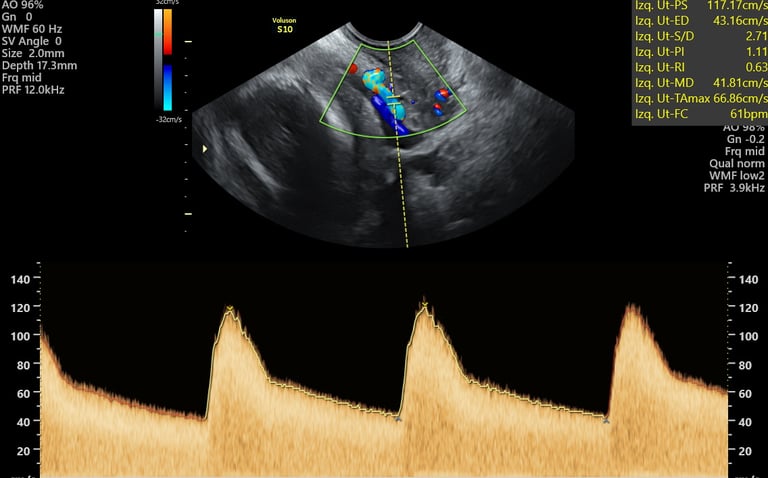

ecografía de crecimiento Doppler

24 - 40 semanas